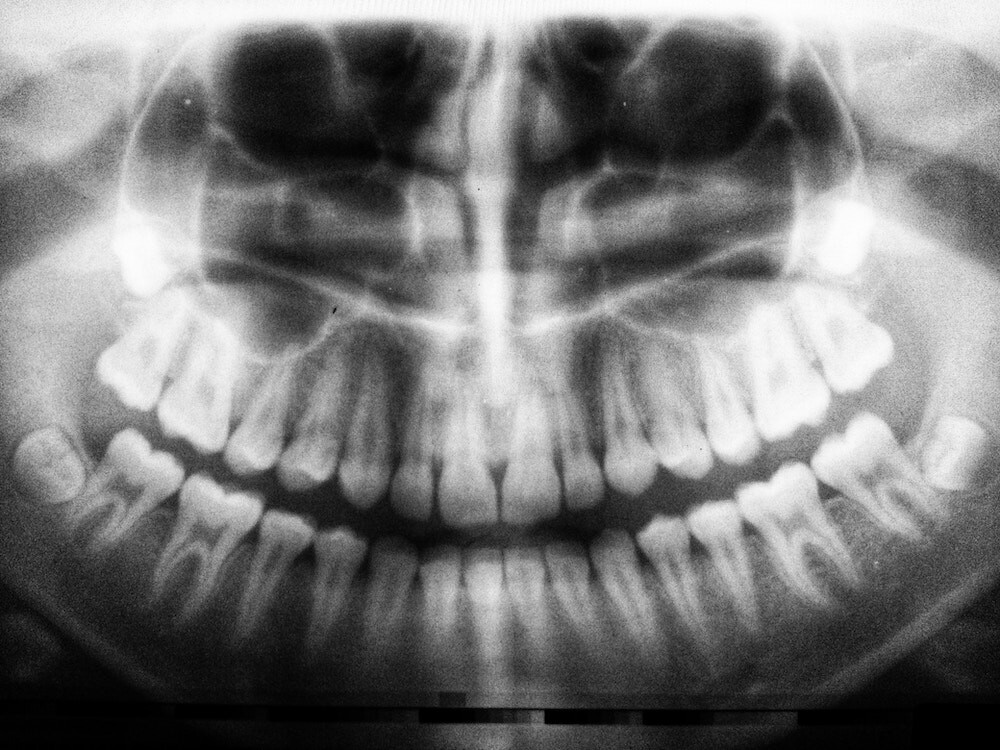

One of the most common places for resorption to occur is in the jawbone.

One of the main reasons for jawbone resorption is the loss of teeth.

When the root is removed, your jawbone no longer receives the stimulus and pressure of chewing. This causes your body to believe that it no longer requires the same bone density in that area.

When a tooth is extracted or lost, up to 25% of bone density can be lost in the first year — and the process continues. Jawbone loss causes your face to shrink, which may make you appear older than you actually are.